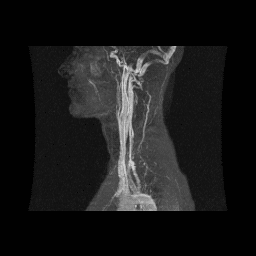

MRI, MRA, and MRV. A two- and three-dimensional image reconstruction, with applications including evaluation and diagnosis of thoracic outlet syndrome (TOS).

Figure 8: This is an anterior image of the coronal abduction external rotation of the upper extremities sequence in Figure 7. This image displays high signal intensity (white) internal mammary (IM) and hepatic veins (H) reflecting increased thoracic and abdominal pressure secondary to decreased venous return on a T-1 sequence. First fascicle of the serratus anterior muscle (FSA), liver (L), left ventricle (LV), stomach (S). With permission from James D. Collins, MD. Read complete article here.